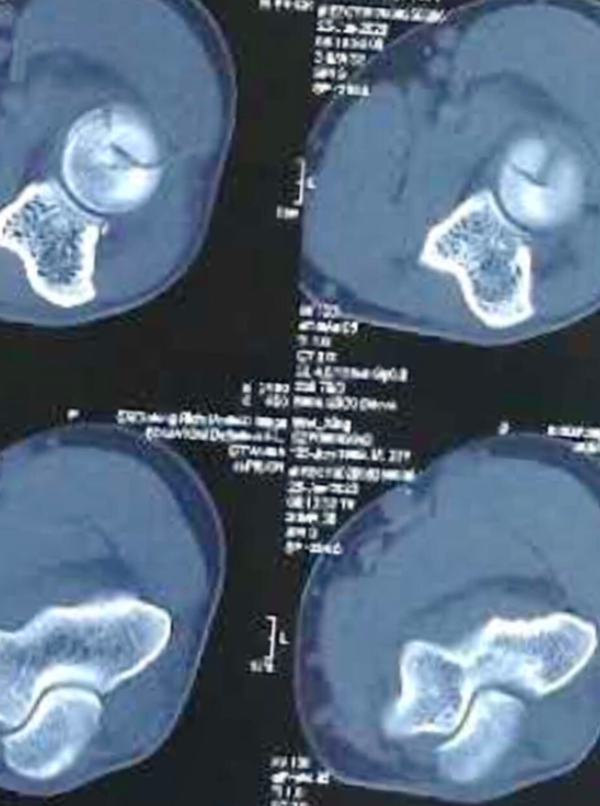

山西医大二院分型,根据CT分型:

依据桡骨头赤道线分型,大部分关节内的桡骨头骨折(Mason2型),都会累及桡骨头的前外1/4。分为:

① 桡骨头前半球骨折;

② 桡骨头后半球骨折。

图2 桡骨头骨折2型赤道前半球骨折

1、CT桡骨头横切面9点至3点作为赤道线,依据桡骨头赤道线分型分为:

①桡骨头前半球骨折;②桡骨头后半球骨折。